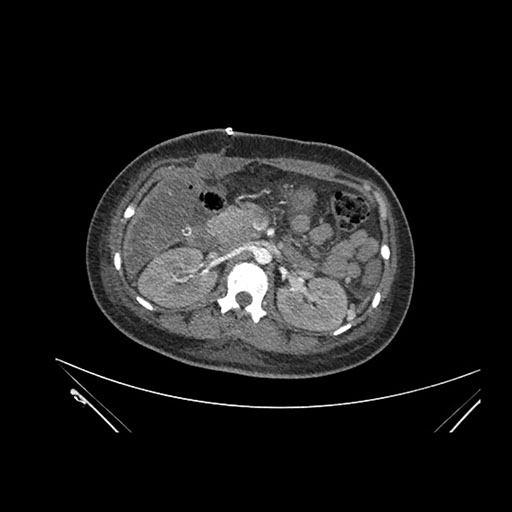

Axial Arterial

Imaging analysis

Based on initial findings, which issue(s) would you be most concerned about?